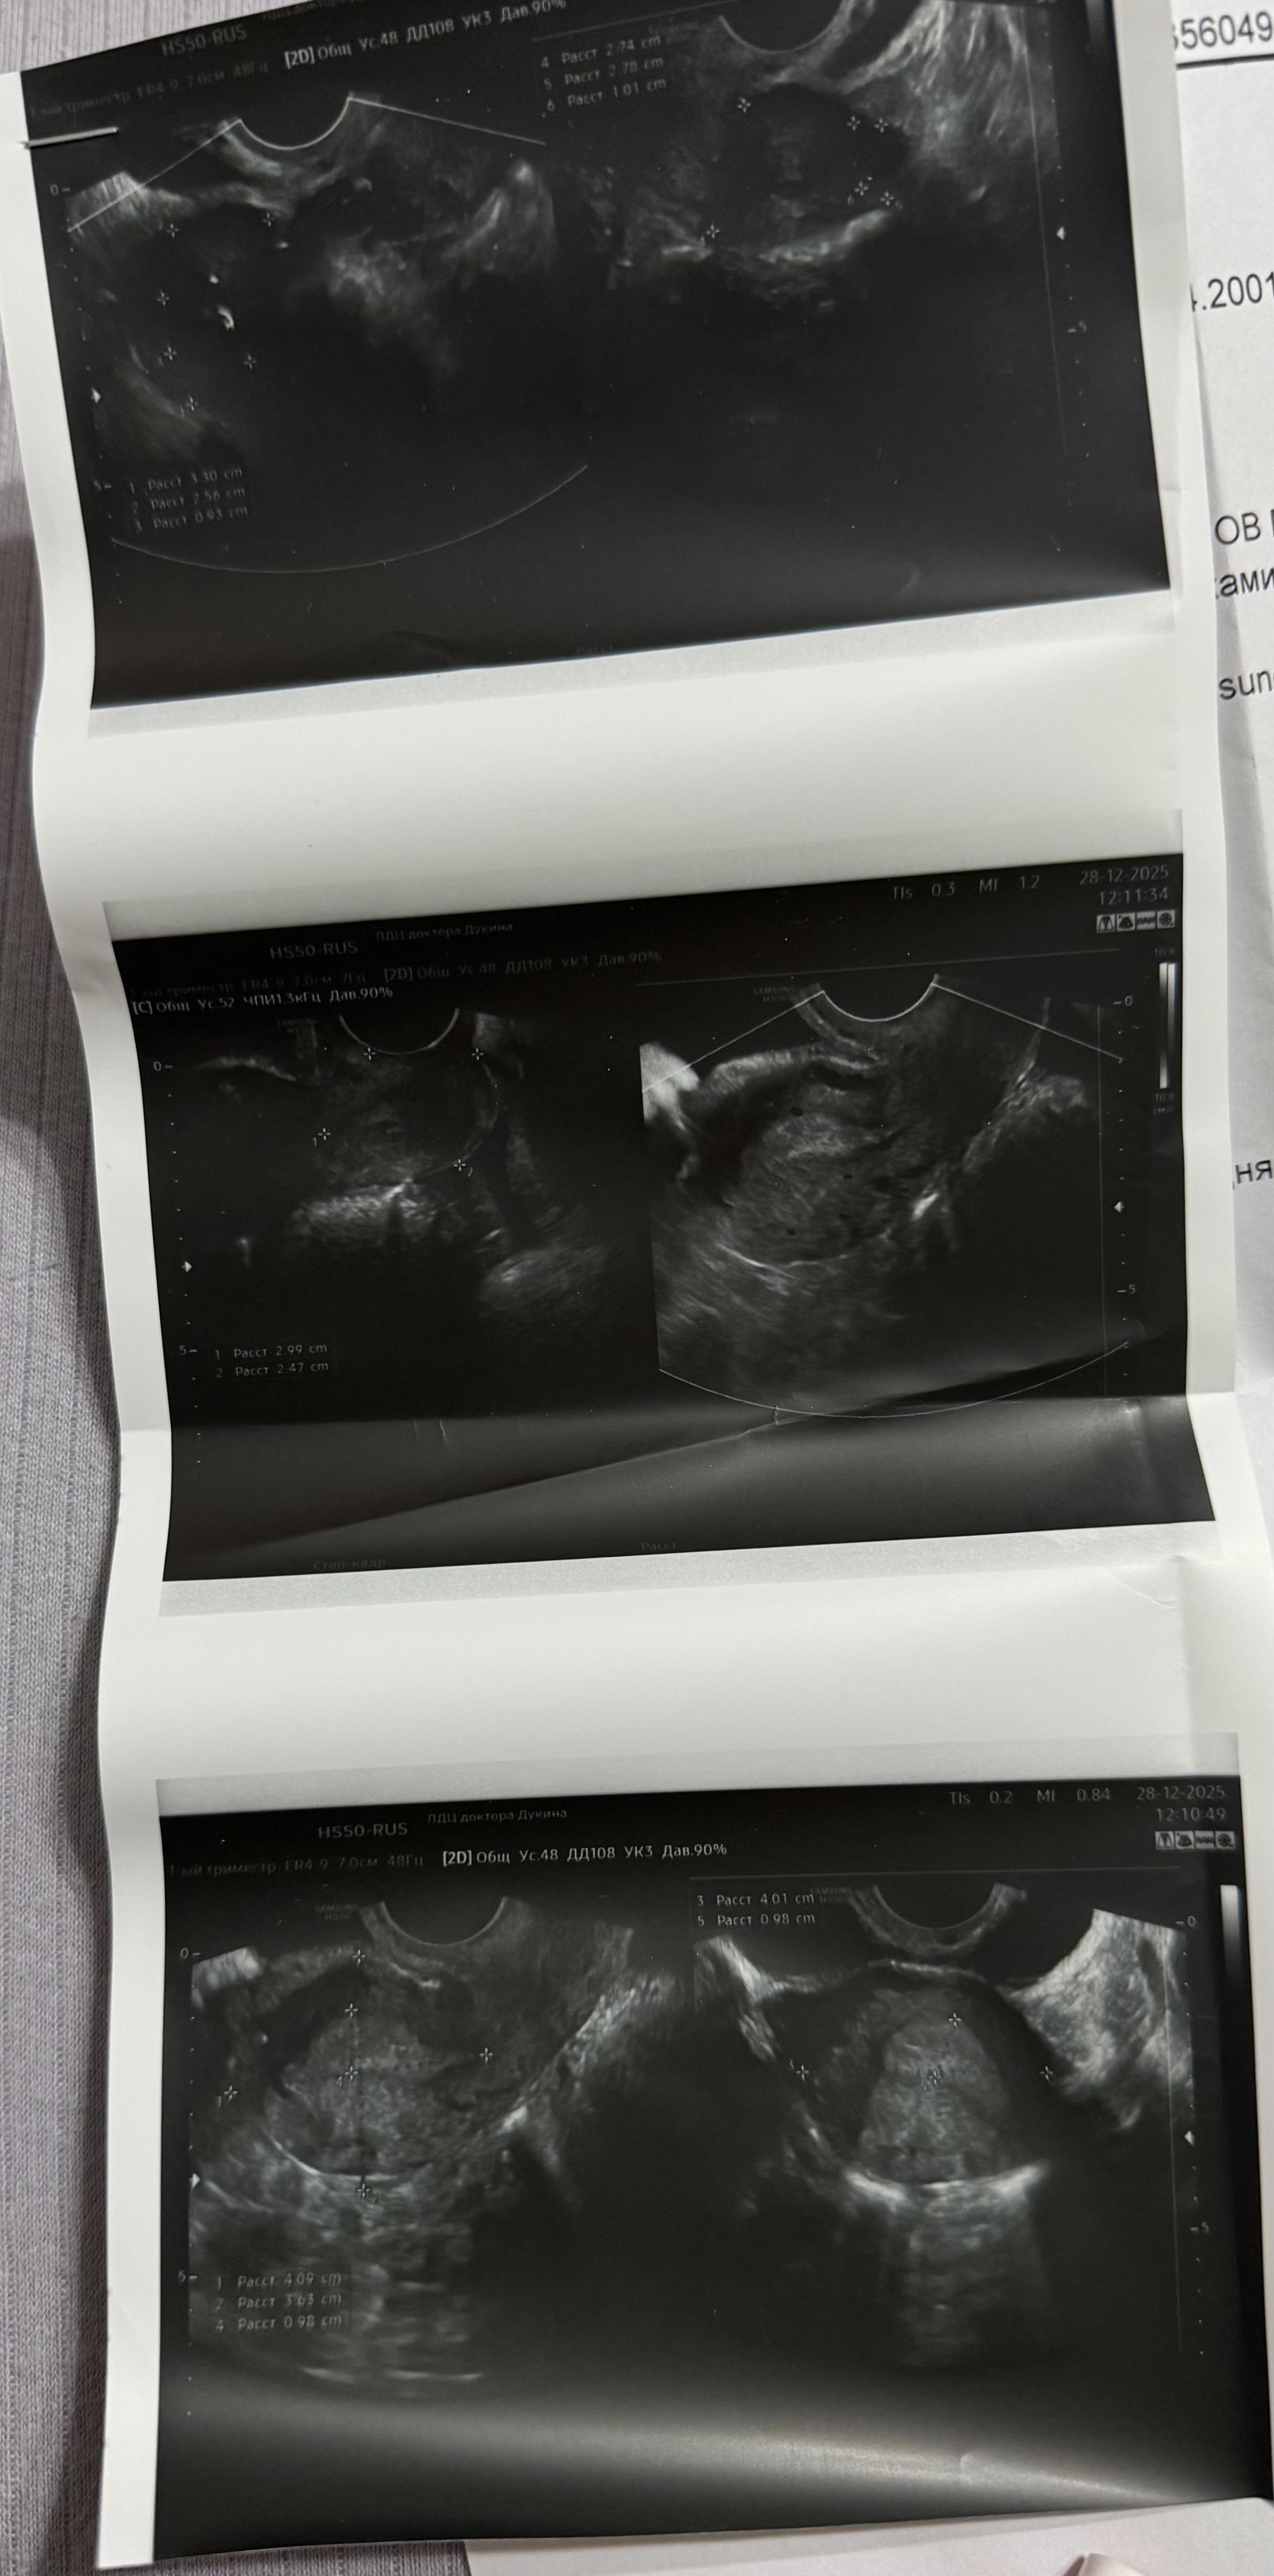

Задержка 8 дней , тесты положительные, но на узи нет плодного яйца, что это может быть ?